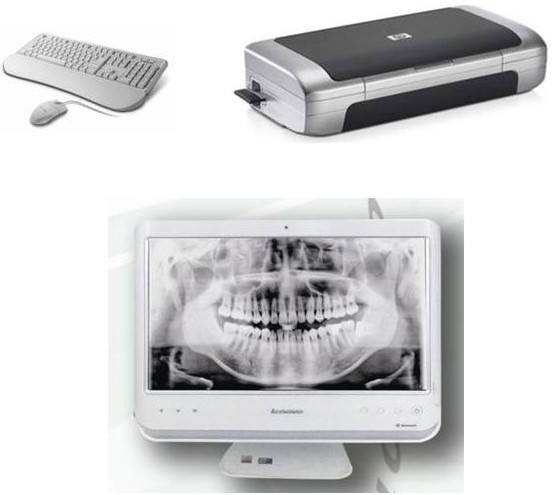

Product : Digital Panoramic Dental X Ray Machine

4 - 10 mA Digital Panoramic Dental X Ray Machine Medical X Ray Machine

4 - 10 mA Digital Panoramic Dental X Ray Machine Medical X Ray Machine Images |